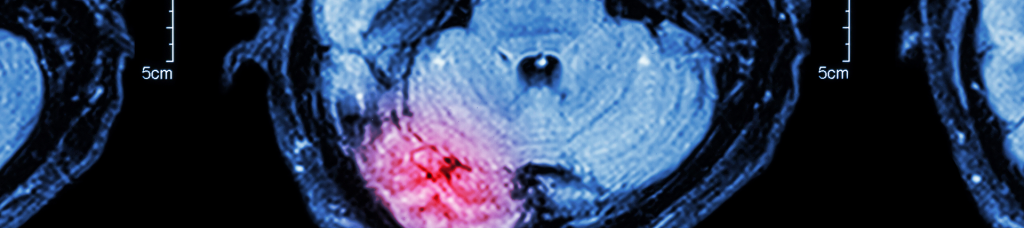

An accident can cause a number of catastrophic injuries, from whiplash to spinal cord, neck, and back injuries. Depending on the severity of the accident, many of these are injuries can heal with time and medical care. Traumatic brain injuries, however, are often devastating and, in many cases, irreversible. A traumatic brain injury, or TBI, is a severe injury to the head that results in serious damage to the brain. In the luckiest of cases, a TBI may merely inconvenience the victim and clear up after a few days of rest. In the worst cases though, TBIs can leave their victims a different person with seriously reduced cognitive functions or even cause them to be in a permanent vegetative state.

TBIs can be classified into one of two groups: open or closed. An open TBI occurs when the skull is penetrated or fractured. It’s usually caused when the head comes into direct contact with another object or surface and is commonly seen in falls, blunt force trauma, or violent attacks. Many times, the object that has broken the skull continues into the brain or breaks apart, causing tiny pieces of debris to embed in the brain tissue. A closed TBI happens when a blow to the head causes the brain to hit the inside of the skull. Closed TBIs can be more serious than an open TBI because the skull strikes a wide area of the brain. This increases the risk for swelling and bleeding on the brain. These symptoms can result in blood clots, coma, and death. A closed TBI may be the result of a hard knock to the head like when a person’s head strikes a car dashboard or windshield.